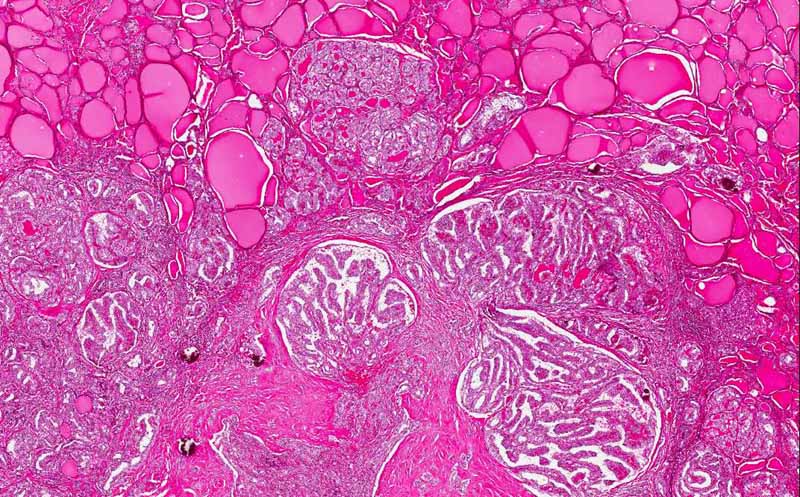

Area 2: Note the papillary growth pattern. It is featured by fine villous or finger like fibrovascular stroma lined by neoplastic epithelial cells. The nuclei are enlarged, often have nuclear grooves and pseudonuclear inclusion. Overlapping of nuclei is also common.

• On mediummagnification, the tumor has papillary growth pattern. (Area 2)

• Compare to the normal thryoid in the same slide (Area 3), the normal structure is disrupted. In addition, the nuclei of the tumor are larger than that of the normal thyroid.